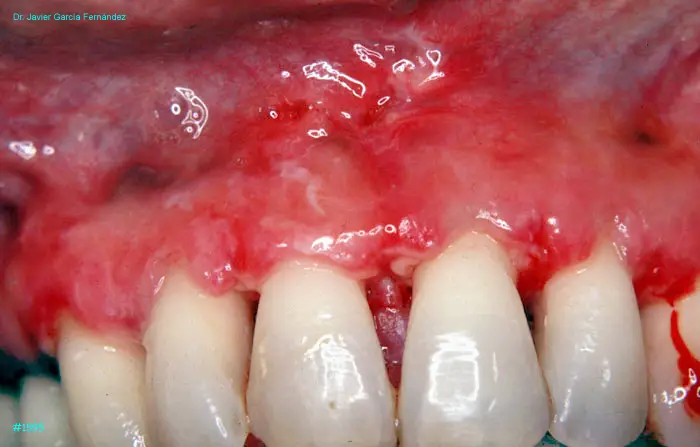

Atlas of Surgical Techniques in Periodontics. Chapter IV. Atlas de Técnicas Quirúrgica en Periodoncia

image 118